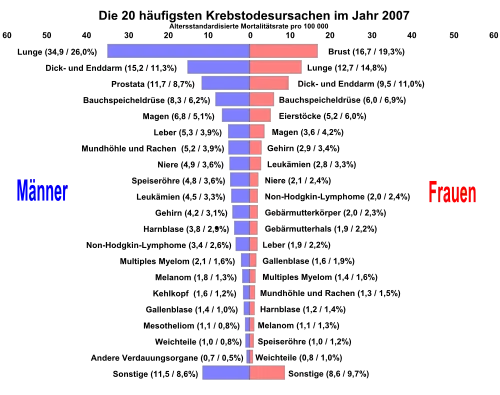

Auf der x-Achse die altersstandardisierte Mortalitätsrate (erster Zahlenwert) und der prozentuale Anteil an den Krebserkrankungen (zweiter Zahlenwert in der Klammer).